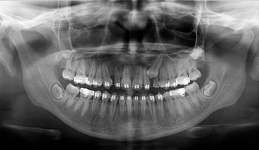

Zásadním faktorem pro úspěšné ošetření je přesná a detailní diagnostika a dokonalé naplánování celého ošetření. K tomu vždy využíváme kombinaci zjištění z klinických vyšetření a rentgenologických dat, které následně zpracováváme v plánovacím softwaru.

Jak pro ošetření stomatochirurgická tak implantologická spolu různými dostavbami kosti je vždy nutné předem znát umístění důležitých anatomických struktur (cévy, nervy, čelistní dutiny). Naše pracoviště jako první v České republice začalo

od roku 2004 používat speciální digitální zubní tomograf 3D DVT NewTom a dále také využíváme nejnovější hybridní CBCT (3D) + 2D přístroj NewTom GiANO, které umožňují 100% diagnostiku množství a kvality kosti a veškerých důležitých anatomických struktur.

Jedná se o nejnovějším přístroj ze skupiny dentálních hybridních CBCT (3D) + 2D (pan i ceph) systémů. Přístroj umožňuje na základě jediného snímkování vytvořit všechny typy RTG zobrazení, které jsou pro lékaře potřebné.

Používaná technologii tzv. „kuželového paprsku“ a speciální senzory pro minimální zátěž při snímkování pacienta

(o více jak 80% nižší dávka proti klasickému CT).

Pomocí tohoto přístroje je možné zjisti skutečnou situaci v čelistních kostech pacienta tedy množství kosti - můžeme změřit skutečnou šířku i výšku kosti, i kvalitu kosti (hustotu) v místě uvažované implantace. 3D (tříprostorové) zobrazení umožňuje

zvýšit prostorovou představu operatéra ještě před vlastní operací a zároveň pacientovi lépe objasnit a ukázat oblast plánovaného zavedení implantátu.

Lékař si vytvoří všechny typy zobrazení potřebných pro naplánování – tedy 2D snímky (panoramatický), příčné řezy i 3D model.

Vidí zde i důležité anatomické útvary – čelistní dutinu, průběh nervu atd. Po proměření množství kosti – šířky i výšky vybere z databáze vhodný typ implantátu a umístí ho do požadované lokality.